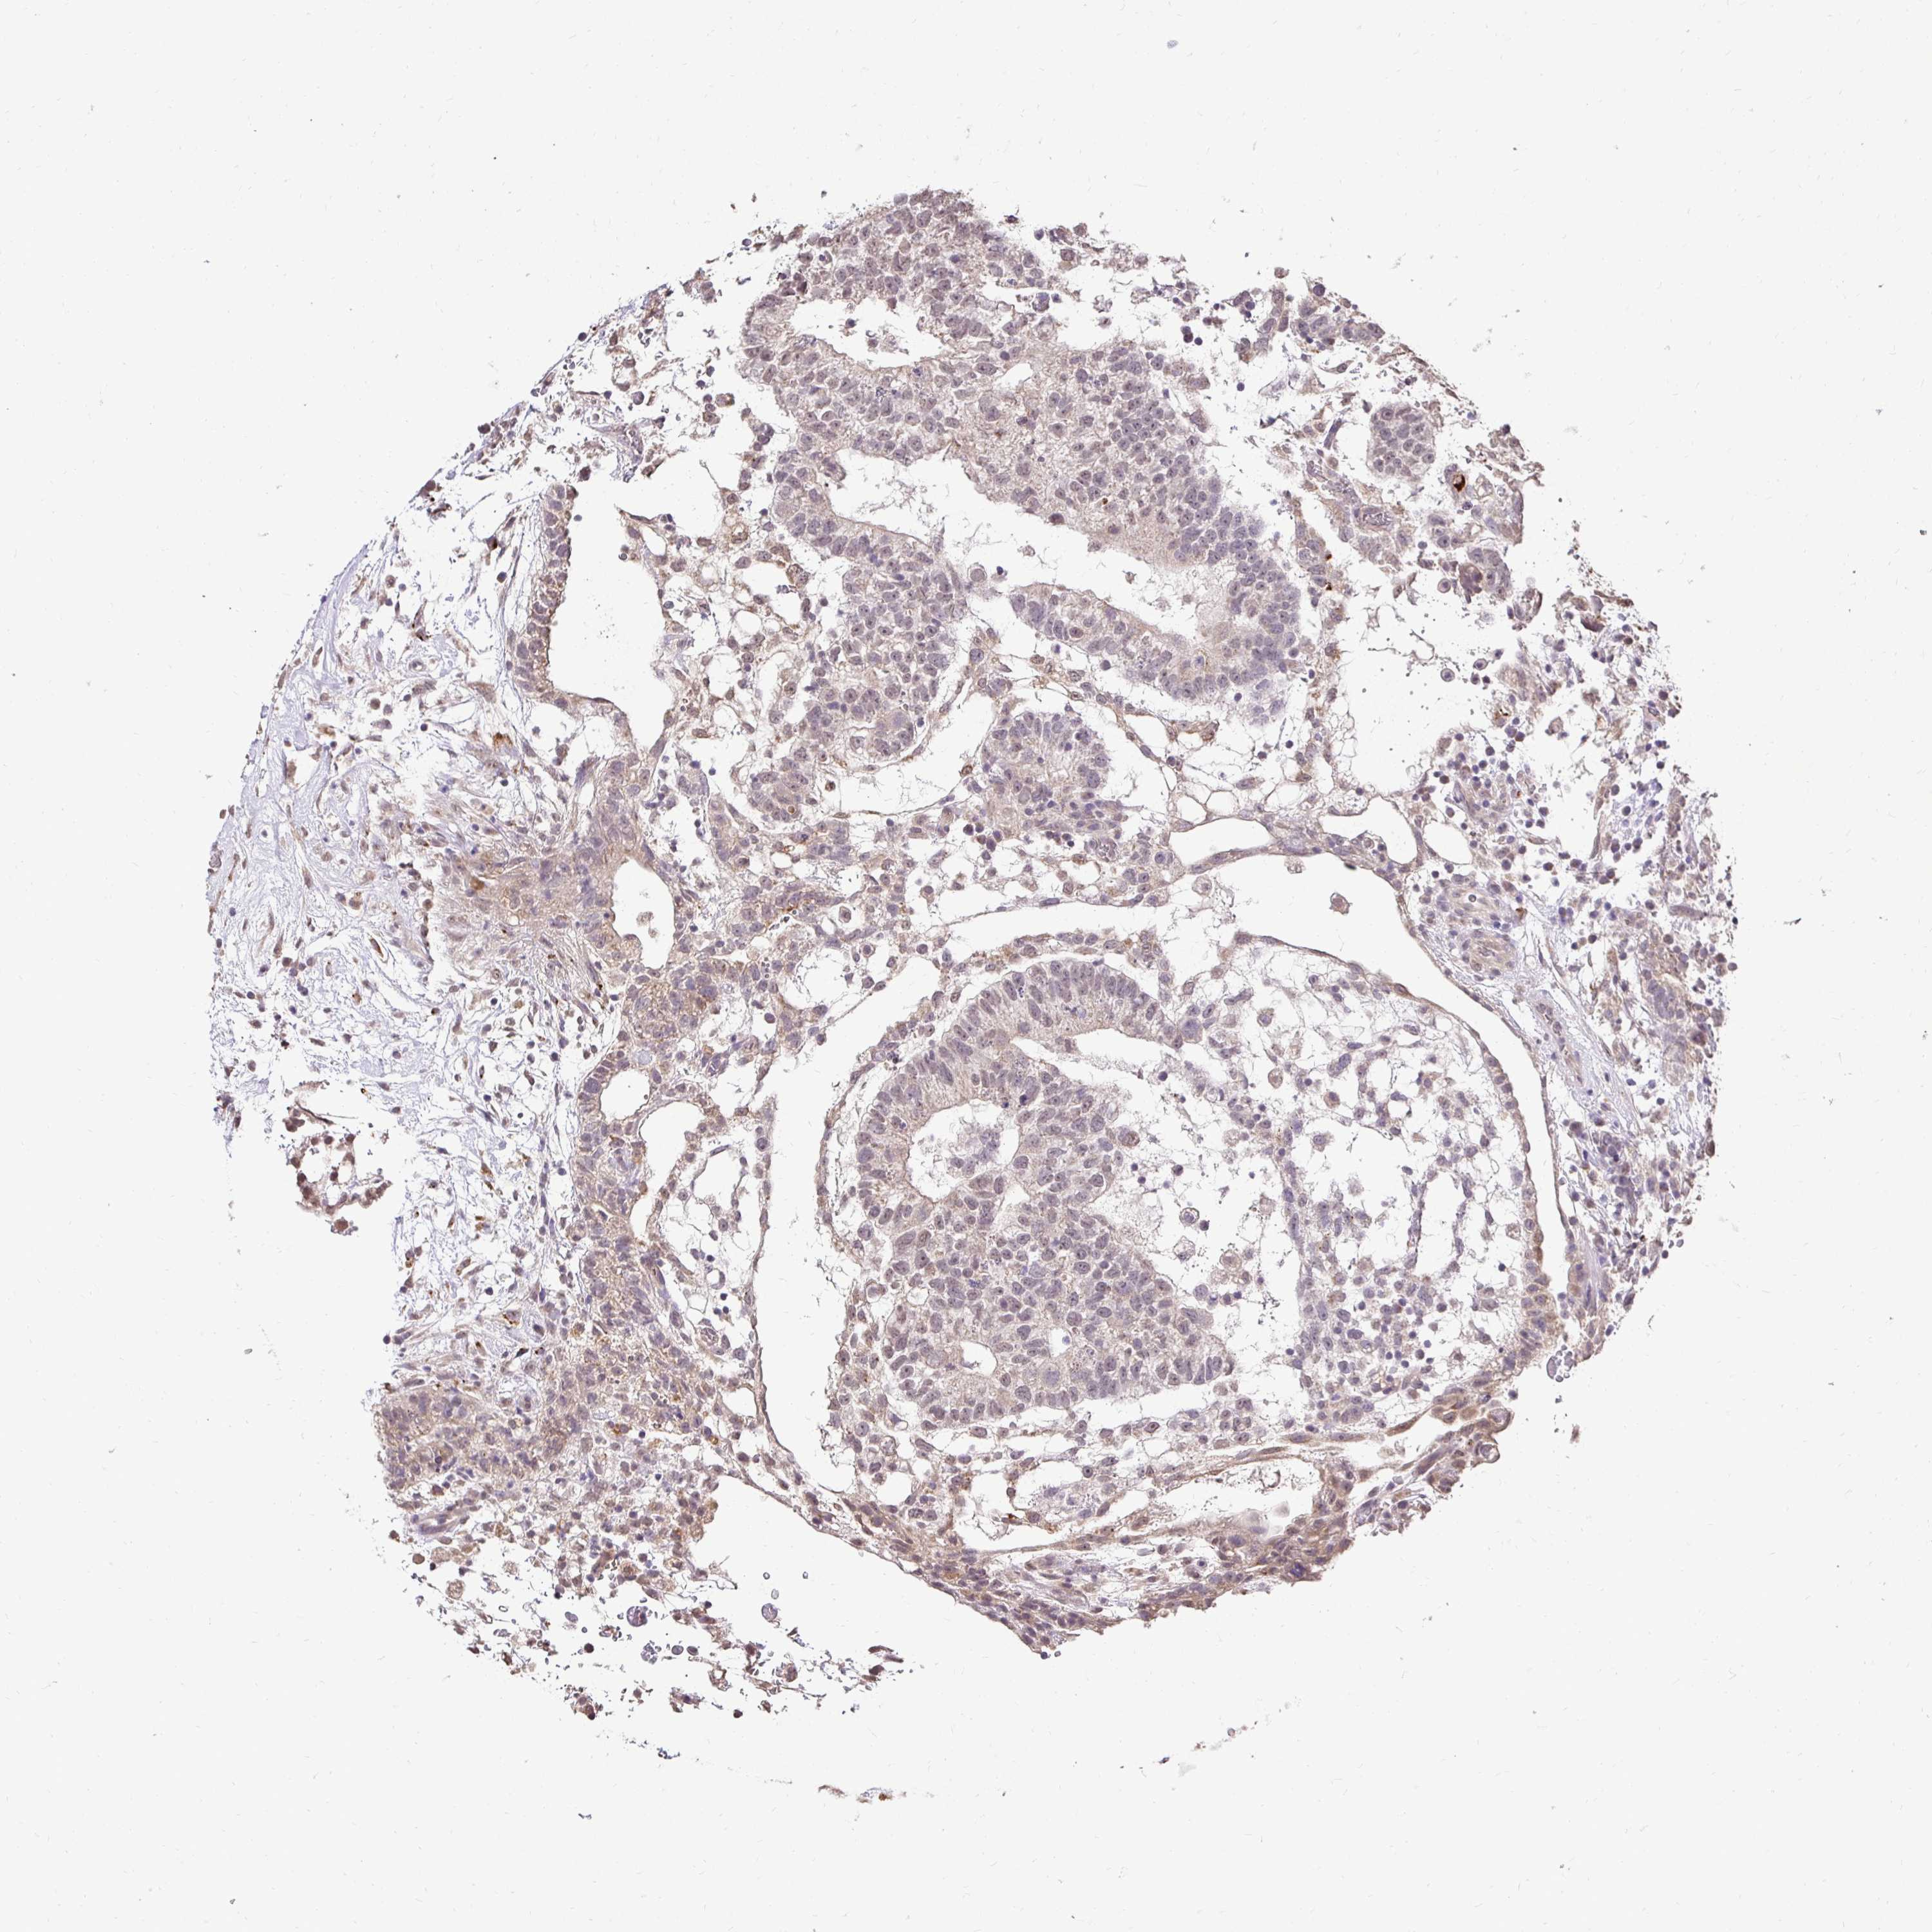

TESTIS CANCER - Protein expressioni

A mouse-over function shows sample information and annotation data. Click on an image to view it in a full screen mode. Samples can be filtered based on level of antibody staining by selecting one or several of the following categories: high, medium, low and not detected. The assay and annotation is described here.

Note that samples used for immunohistochemistry by the Human Protein Atlas do not correspond to samples in the TCGA dataset.

Antibody stainingi

Antibody staining in the annotated cell types in the current human tissue is reported as not detected, low, medium, or high, based on conventional immunohistochemistry profiling in selected tissues. This score is based on the combination of the staining intensity and fraction of stained cells.

Each image is clickable and will lead to virtual microscopy that enables deeper exploration of all samples and also displays staining intensity scores, fraction scores and subcellular localization as well as patient and tissue information for each sample.

Antibody HPA053111

Antibody HPA061001

Staining

High

Medium

Low

Not detected

Intensity

Strong

Moderate

Weak

Negative

Quantity

>75%

75%-25%

<25%

None

Location

Nuclear

Cytoplasmic/membranous

Cytoplasmic/membranous,nuclear

Seminoma, NOS

Carcinoma, Embryonal, NOS

Teratoma, malignant, NOS